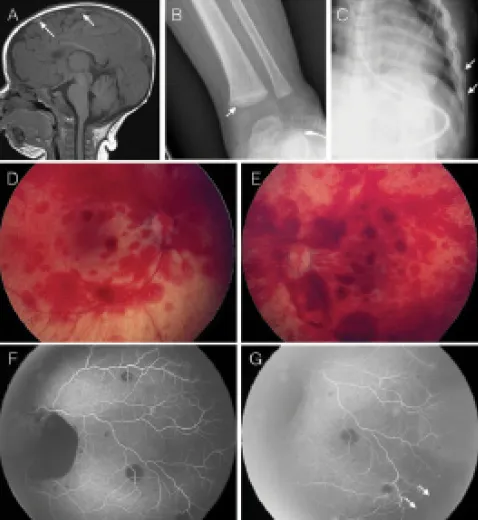

⭐ Retinal hemorrhages (RH) are present in ~75% of AHT cases; often bilateral, multilayered, and extending to the periphery (ora serrata).

- Hallmark of Abusive Head Trauma (AHT); often bilateral & asymmetric.

- Types & Location:

- Intraretinal: Dot, blot, flame-shaped (most common).

- Preretinal (Subhyaloid): Boat-shaped, can form pseudo-hypopyon.

- Vitreous: May obscure fundal view.

- Subretinal: Less frequent.

- Classic AHT Pattern: 📌 B-MEN

- Bilateral (though often asymmetric).

- Multilayered (intra-, pre-, sub-retinal).

- Extensive (reaching ora serrata).

- Numerous ("too numerous to count" - TNTC).

- Pathophysiology: Vitreoretinal traction from repetitive acceleration-deceleration forces (shaking).

- Associated Posterior Segment Injuries:

- Traumatic retinoschisis (esp. circumferential perimacular folds).

- Optic nerve sheath hemorrhage.

- Macular holes/folds.

- Chorioretinal scars (late finding).

⭐ Multilayered retinal hemorrhages extending to the ora serrata are highly specific for AHT, reported in 65-95% of cases.

- Systemic workup: Skeletal survey (if <2 yrs), Neuroimaging (CT/MRI), Coagulation profile.